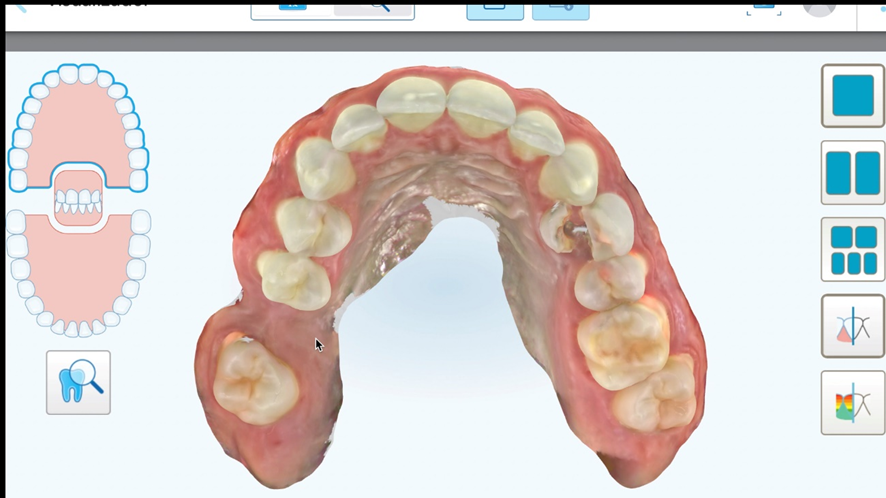

Paciente do gênero masculino, 37 anos, leucodermo, compareceu ao consultório odontológico (Porto Velho/RO – Brasil), queixando-se de ter quebrado o dente do lado esquerdo. No pré-tratamento foi realizada a anamnese do paciente e identificado que o dente 24 estava fraturado. Foram realizadas as fotos iniciais, solicitado exames por imagem de escaneamento digital e tomografia Cone Beam da região.

Para o planejamento reverso foi realizado escaneamento digital e obtido o modelo digital da boca do paciente, assim como também a tomografia Cone Beam da regão para a confecção do guia cirúrgico. Foi planejando também a necessidade de realizar enxerto ósseo do tipo heterogêneo com colágeno para o preenchimento do GAP da região, visando assim criar um bom perfil de emergência e reduzir a chance de perda volumétrica. Foi planejado também um provisório de PMMA a partir de software de planejamento e enceramento digital 3D (Exocad).